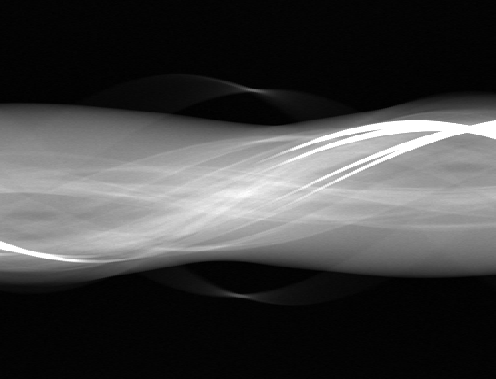

In practice, the complex wavelet transform is an effective tool for extracting singularities from a signal, as previously demonstrated for CT wavefront set extraction in [39]. In images and volumetric data, large-magnitude wavelet coefficients typically occur near jumps and edges. See Fig. 1 for an example of a sinogram containing two metal inserts, where the sum of the absolute values of the wavelet coefficients reveals the corresponding metal boundaries.

| 3D sinogram | ![]() |

![]() |

|---|---|---|---|---|

|